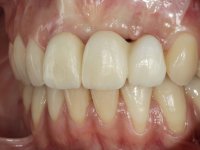

In the initial phase, it was proposed to the patient to perform the surgical implant exposure and after clinical evaluation, make prosthetic decisions. Once the healing screw was placed and the soft tissues were healed, an inadequate position of the implant was found. In view of the dramatic situation, the patient was proposed to remove the implant and put a new one after tissue regeneration. This proposal was rejected by the patient, who suggested temporary rehabilitation of the current implant. A new proposal was then made, to rehabilitate the implant, consisting of a screwed abutment, and on this, the placement of an acrylic crown with coronal and gingival components. After 6 years with the provisional treatment, the patient appeared in consultation with an abscess in tooth 1.1. After clinical and imaging analysis, it was decided to remove teeth 1.1 and 2.2, submerge the implant, place two implants at the site of 1.1 and 2.2 and perform adequate tissue regeneration. Temporization would be done with a provisional 3-element bridge, adhered with a net to the neighboring teeth. After osseointegration, definitive rehabilitation would be done with a 3-element bridge, including zirconia infrastructure and ceramic cover.

The surgical implant exposure and the healing screw placement proved to be a negative surprise regarding its position. Since the proposed removal of the implant was refused, we advanced to its provisional rehabilitation. An open tray impression technique was done, and a screwed abutment with a coronal and gingival component and an acrylic crown were made in the laboratory, using these two components. The provisional crown was placed in the mouth until a final decision was made. Six years passed before the patient returned to the clinic with an abscess on tooth 1.1. The choice to remove teeth 1.1 and 2.2 was made, to create a provisional 3-element bridge with a net to be adhered to the adjacent teeth. Surgery was planned and performed, placing the two implants at the site of 1.1 and 2.2, and the implant at the 2.1 site was cut with the objective of submerging it, while adequate tissue regeneration was performed (Surgical Work performed By Dr. Manuel Neves). During osseointegration, the patient used the fixed provisional bridge. A first impression was made for confection of a zirconia screwed provisional bridge, which worked the soft tissues for twelve weeks. The definitive impression was made with the individualisation of custom impression copings. Final rehabilitation was done with ceramized abutments, and also a bridge with zirconia infrastructure and ceramic cover. Due to the inclination of the implant placed at the site of tooth 1.1, the bridge required cemented fixation.